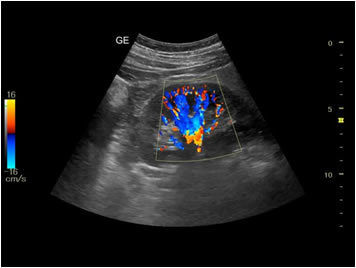

Our professionals at EWH are trained to use state of the art ultrasound technology to provide ultrasound diagnoses